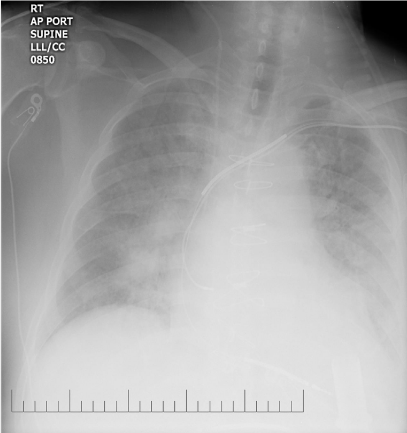

He was administered a recombinant tissue plasminogen activator, Alteplase 70 mg IV X 1 (0.81 mg/kg x 86.2 kg) over 1 minute, followed by 7.7mgs (0.09mg/kg x 86.2kg). His LVAD parameters post-Alteplase infusion were: RPM- 10,000, Power- 7.7, Pulsatility index-3.5, Flow-6.4 L/min. 24-hours post completion of Alteplase infusion; he was started on intra-venous Heparin continuous infusion (--units) with no bolus. CT-Head scans were obtained serially, prior to initiating heparin therapy and during the 1st week and showed evolving ischemic infarct with no intra-cranial hemorrhage (Figure 4). On day 4 with no further decrease in his LVAD power (Table 1) he was started on a continuous infusion of Eptifibatide at 1mcg/kg/min that was increased to 1.5mcg/kg/min for days 6, 7 and continued at 1mg/kg/min for days 8-19. During this time his hemodynamics also improved allowing inotropic support with Milrinone to be weaned off. CT-Head performed on day 16 showed completed ischemic infarct with small stable sub-arachnoid hemorrhage (Figure 5).

Figure 4 Chest- X Ray Post- Thrombolytic Infusion showing

a) Decreased pulmonary vascular congestion

b) Unchanged LVAD cannula position from baseline